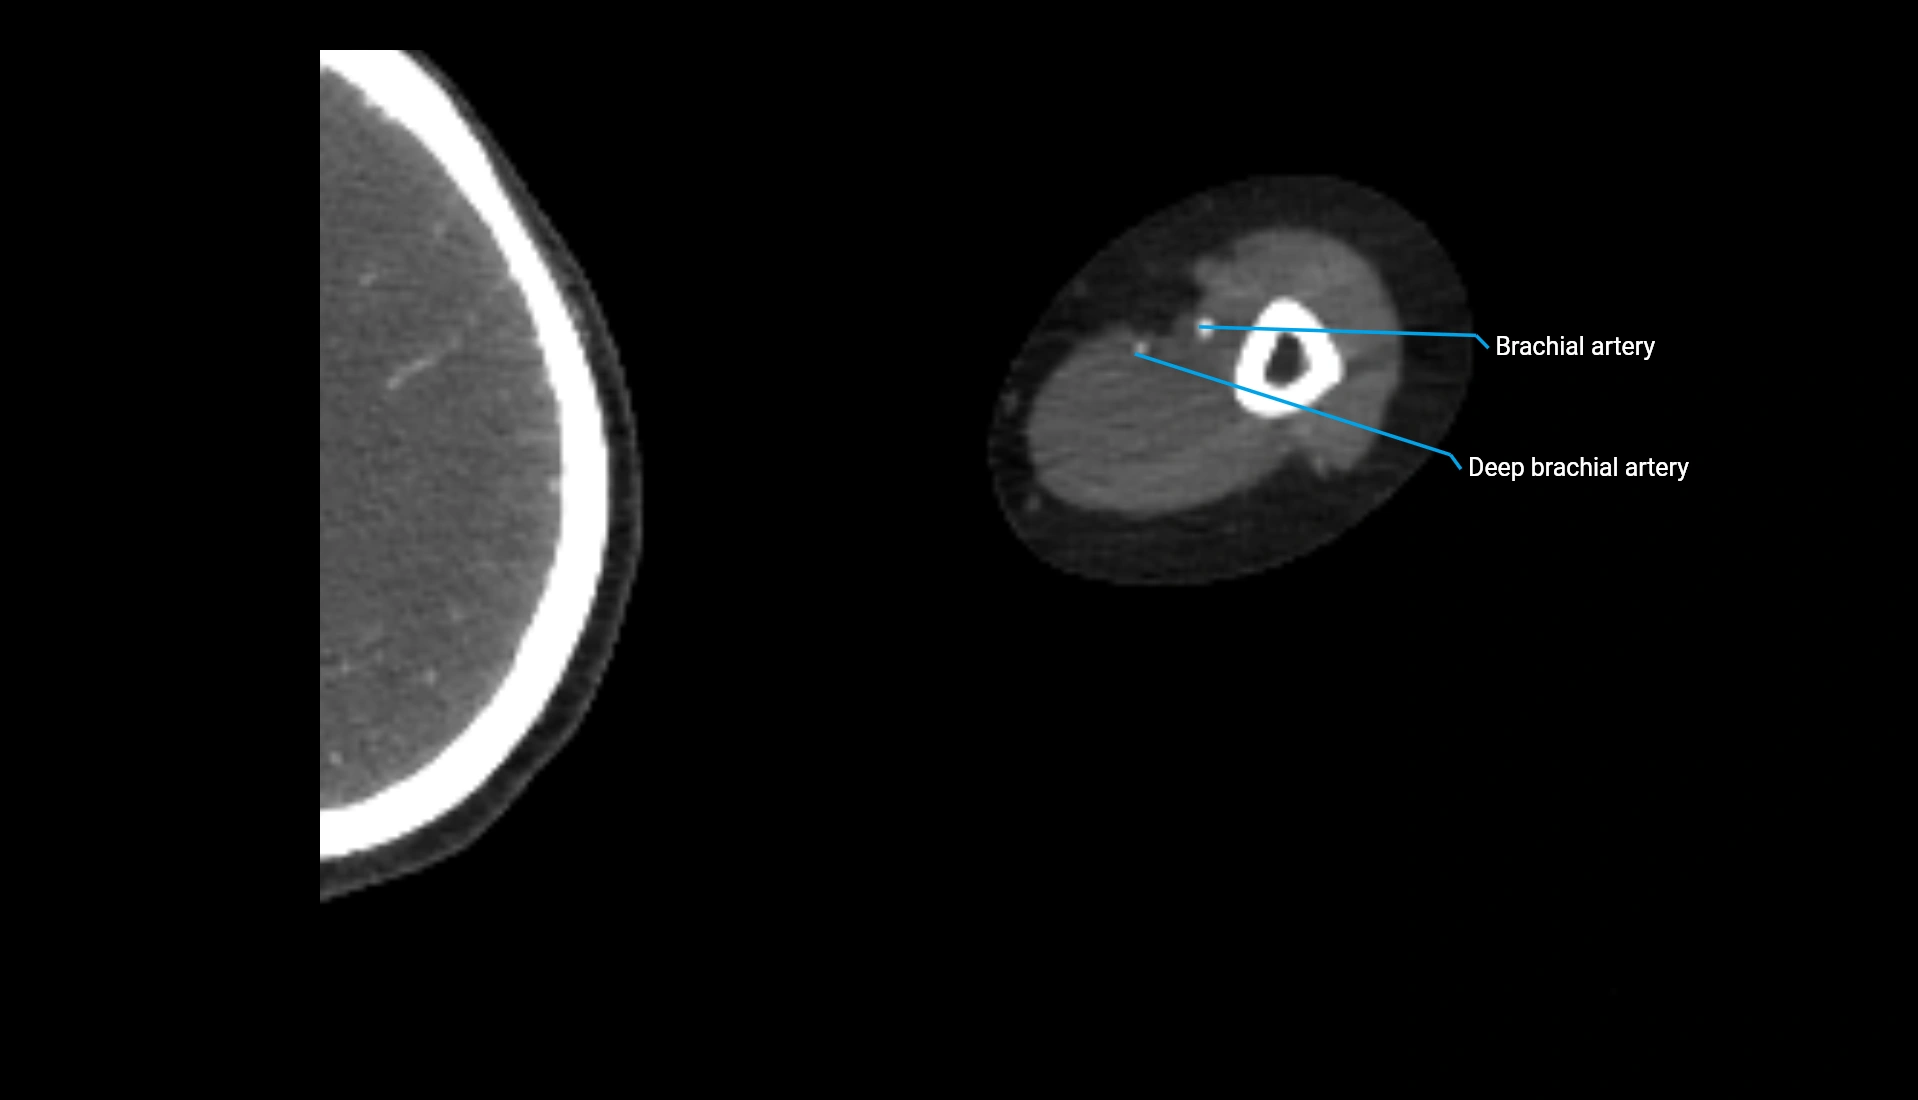

CT Appearance

Non-Contrast CT:

• Cortex: High-density, sharply defined

• Subchondral bone: Dense cancellous matrix

• Articular surface: Smooth concave contour articulating with the capitellum

• Excellent for evaluating bone integrity, alignment, and subtle fractures